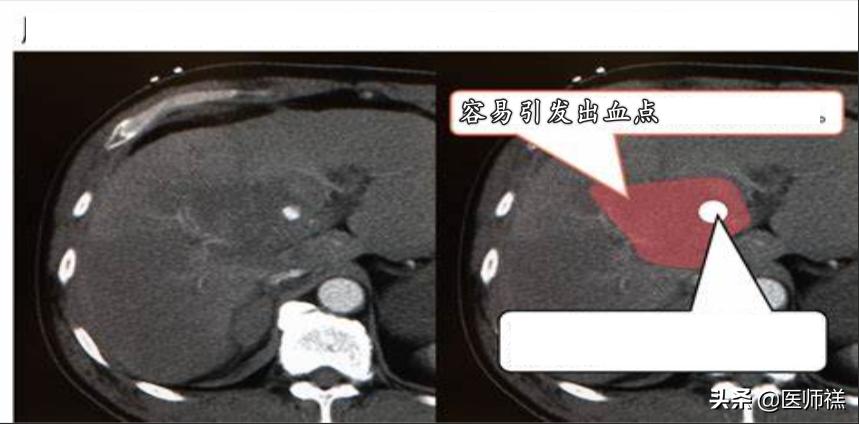

- 并发症1:腹腔出血。腹腔出血一般发生在凝血功能障碍的患者身上,由于穿刺过程中无法保证不损伤血管。出现出血点意味着危险的发生。这种情况下如果不配合出血点的消融,患者很容易出现大出血的可能。